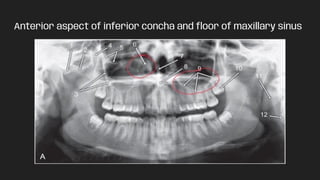

Anterior aspect of inferior concha and floor of maxillary sinus

Anterior aspect ofinferior concha and floor of maxillary sinus